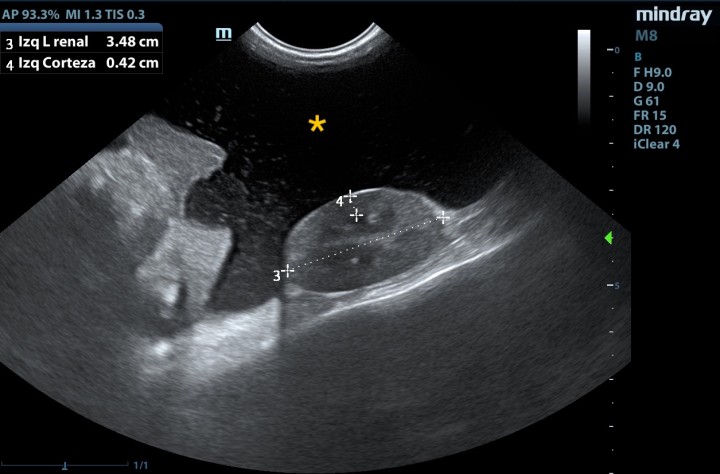

Se realizaron analítica sanguínea, proteinograma sérico y ecografía abdominal. En los resultados (Tabla 1) se observó trombocitosis (plaquetas: 639 x 103/µl, ref: 175-500 x 103/μl) leucocitosis con neutrofilia sin desviación a la izquierda y monocitosis (leucocitos: 26,7 x 103/µl, ref: 5,5-19,5 x 103/μl; neutrófilos: 20,8 x 103/µl, ref: 2,5-12,5 x 103/μl; monocitos: 2,6 x 103/µl, ref: 0-0,850 x 103/μl), hiperbilirrubinemia (bilirrubina: 0,60 mg/dl, ref: 0,1-0,5 mg/dl), hipocloremia (cloro: 110 mmol/l, ref: 115-128 mmol/l), hiponatremia (sodio: 143 mmol/l, ref: 148-157 mmol/l), hiperkalemia (potasio: 5,64 mmol/l, ref: 3,5-5,1 mmol/l), aumento AST (AST: 74 U/l, ref: 6-44 U/l) y disminución de urea (urea: 37 mg/dl, ref: 40-70 mg/dl). En el proteinograma (Fig. 1) se observó un aumento de las proteínas totales (proteínas: 82 g/l, ref: 55-71 g/l) con aumento de las alfa-2 globulinas (alfa-2 globulinas: 14,8 g/l, ref: 4-9 g/l) y disminución de las beta-globulinas (beta-globulinas: 8,1 g/l, ref: 9-19 g/l). Se realizó una ecografía abdominal en la que se observó abundante líquido libre abdominal y la presencia de una masa heterogénea en la zona pancreática, además del incremento de la ecogenicidad y aspecto heterogéneo del peritoneo, lesiones nodulares hepáticas, y efusión pleural escasa (Figs. 2 y 3).

Figura 2

Presencia de líquido libre abdominal (*).

La ecografía abdominal realizada en el paciente puso de manifiesto la presencia de abundante líquido abdominal libre, así como de una masa abdominal asociada a la zona pancreática. En gatos, el diagnóstico ecográfico de neoplasias pancreáticas puede ser complejo y en ocasiones difícil de diferenciar de otros procesos pancreáticos, como la hiperplasia, aunque la presencia de una masa mayor a 2 centímetros se ha relacionado con la presencia de neoplasia.2